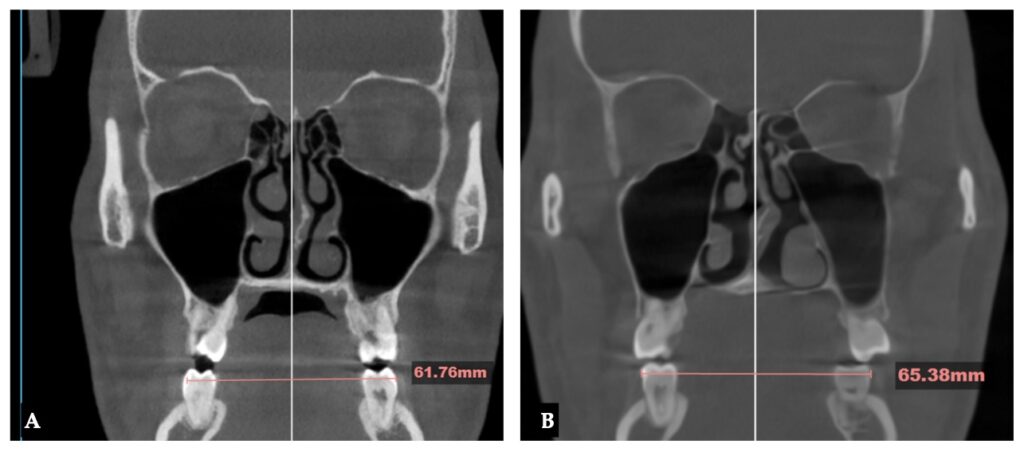

상악골확장 후 3차원 CT를 촬영해

뼈의 변화량을 확인하고

남은 공간을 계산하여

최종 치료 계획을 수립하게 됩니다.